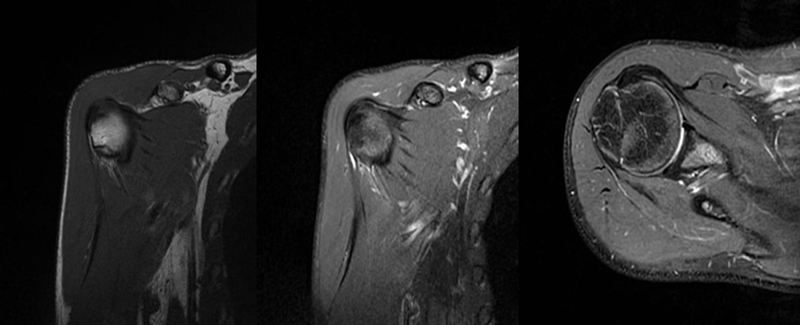

2、MRI检查

MRI目前是诊断肩袖疾病中最常用的检查,可以直观的观察肩袖肌腱。

图21 斜冠状位(临床常用)a.T2,b.T1

图22 斜矢状位 a.冈上肌出口,肩袖诊断不如斜冠状位;b.冈上肌及肌腹脂肪浸润成度,评估手术与否

图23 横断位a.正常肩胛下肌;b.肩胛下肌损伤

图24 a.肩袖全层撕裂;b.正常MRI

图25 巨大肩袖损伤(冈上肌)